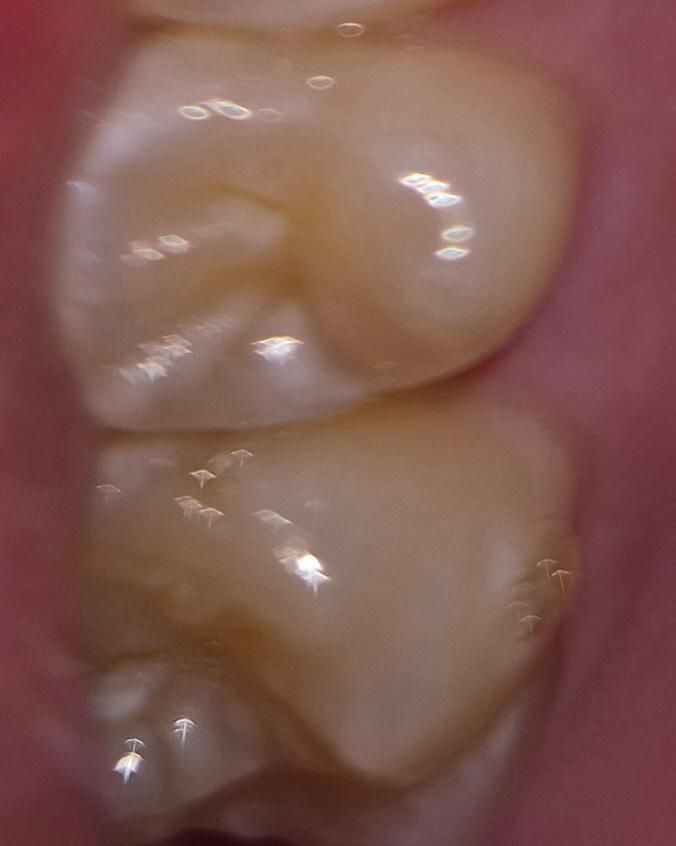

16번치아 얕은 충치 처리 후 레진치료 했는데 레진이 떨어진걸까요?

• 1번 째 사진